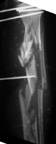

Tibia Fx ForumCase 1

I would appreciate treatment suggestions.My patient is a 30 year old with a very comminuted tibia fracture 6 weeks ago.It was grade 3B open. Initial treatment included irrigation, debridementClick images to enlarge.

and a hybrid external fixator including femur, tibia and foot. Screwswere placed in the plateau and plafond and a free flap plus STSG. Theskin is ok but atrophic. The femoral pins were removed and knee motionstarted at 6 weeks. There is no sign of callus. There is one pin inthe one large fragment of the diaphysis. All the pieces are lined upreasonably well. The XF pins are ok. Suggestions? Thank you.